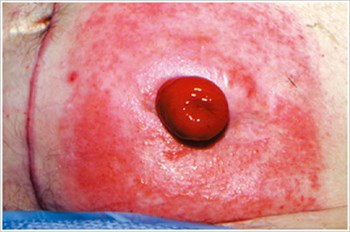

Pyoderma Gangrenosum

Popis/příčiny:

Zánětlivé kožní onemocnění, které se často vyskytuje u pacientů se zánětlivým onemocněním střev (IBD), jako je Crohnova choroba nebo ulcerózní kolitida.

Symptomy:

- Nepravidelně tvarované, červené, bolestivé, infikované vředy, s červenými až fialovými svinutými okraji; se objevují na nohou, hýždích, obličeji a peristomální oblasti.